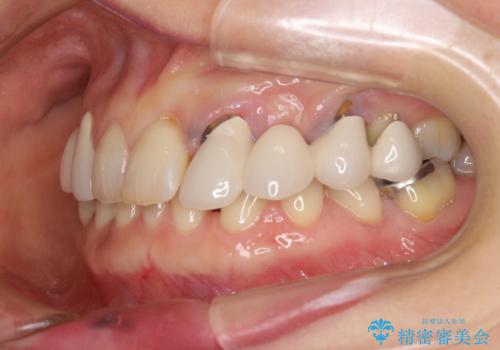

- 割れていると言われて放置してしまった歯や、前歯のデコボコなどが気になるとのことで来院された患者様です。

左上の歯は割れてしまっており、抜歯のうえインプラント治療が必要であり、他にも抜歯の必要な歯がある状態でした。

上顎はほぼ全ての歯をセラミッククラウンにて補綴治療を行う必要があるため、気になるデコボコや深い咬み合わせを改善するために下顎と上顎の臼歯部の矯正治療を行うこととしました。

並行して左下にはインプラントを埋入し、矯正治療を終えると同時に補綴治療を行うこととしました。

過蓋咬合(下顎前歯が隠れてしまうほどの深い咬み合わせ)のため、スムーズに歯が動かず矯正治療に時間がかかりましたが、無事に仕上げることができました。